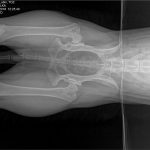

Wracamy do znanej czytelnikom Julki. TOZ ponownie zbiera fundusze na pomoc dla suczki. Julka żyje w ciągłym bólu – problemy z biodrami utrudniają jej bieganie i skakanie. U psiaka zdiagnozowano bowiem dysplazję stawów biodrowych. Dodatkowo ma silną anemię i szybko traci na wadze. Początkowo planowano przeprowadzenie operacji, ale teraz nadarzyła się inna szansa na odzyskanie zdrowia – syntetyczna wiskoproteza.

Niestety stan zdrowia suczki od początku był zły. Julka wymagała długiego procesu leczenia i opieki profesjonalistów. Na początku 2017 r. trafiła do hoteliku w Warszawie, gdzie miała mieć zapewnioną opiekę behawioralną oraz weterynaryjną. Tam zdiagnozowano u suczki ciężką dysplazję stawów biodrowych oraz bardzo silną anemię.

– Julka dziś jest piękną, łagodną 25-kilogramową kuleczką. Jej wdzięczność za nowe życie powala na kolana. Suczka odzyskała równowagę emocjonalną, ale wciąż przeszkodą są problemy natury fizycznej. Dysplazja stawów biodrowych utrudnia suni bieganie, skakanie i inne czynności. Wcześniej sądziliśmy, że będzie musiała przejść operację. Teraz znaleźliśmy nowe rozwiązanie – opowiada Karolina Lorenc.

Pomoc dla Julki czeka na nią w Gdańsku lub bliżej – we Wrocławiu. Nowa metoda Noltrex to syntetyczna wiskoproteza o właściwościach podobnych do mazi stawowej. Jej bardzo wysoka gęstość wspomaga amortyzacją stawu, zapobiegając otarciom, niwelując ból, a zawarte w niej jony srebra działają bakteriostatycznie. Wiskoproteza pomaga zachować integralność chrząstki stawowej, co jest szczególnie istotne w przewlekłych chorobach zwyrodnieniowych.